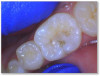

Fig 4d. Carious lesion on tooth No. 19 requiring

a deep excavation in which an indirect pulp cap was performed using a light curable resin-modified calcium silicate (Bisco TheraCal LC), and

the tooth was subsequently restored in two separate steps using Kerr SimpliShade Bulk Fill Flow followed by SimpliShade Bulk Fill Packable

as the capping layer.

Fig 4d.

Figure 4a through Figure 4e show the technique using a bulk fill flow with a bulk fill capping layer. There was a carious lesion on tooth No. 19 requiring a deep excavation of decay close to the pulp and cotton roll isolation. Practitioner did an indirect pulp cap using a light curable bioactive syringeable flowable that can be used for direct and indirect pulp capping, and then applied a layer of the bulk fill flow, which offered a good glossy appearance without polishing. Kerr SimpliShade Bulk Fill Flow and Bulk Fill Packable were used. Although most bulk fill flows are transparent, this one successfully blocks the white opaque resin-modified calcium silicate filled liner (Bisco TheraCal LC). The practitioner used bulk fill packable (Kerr SimpliShade Bulk Fill) as the capping layer in a single increment. In the author's opinion, this single shade bulk fill system offers excellent esthetics and gives an outcome similar to layering. The patient reported no post operative sensitivity or discomfort after the restoration was performed.